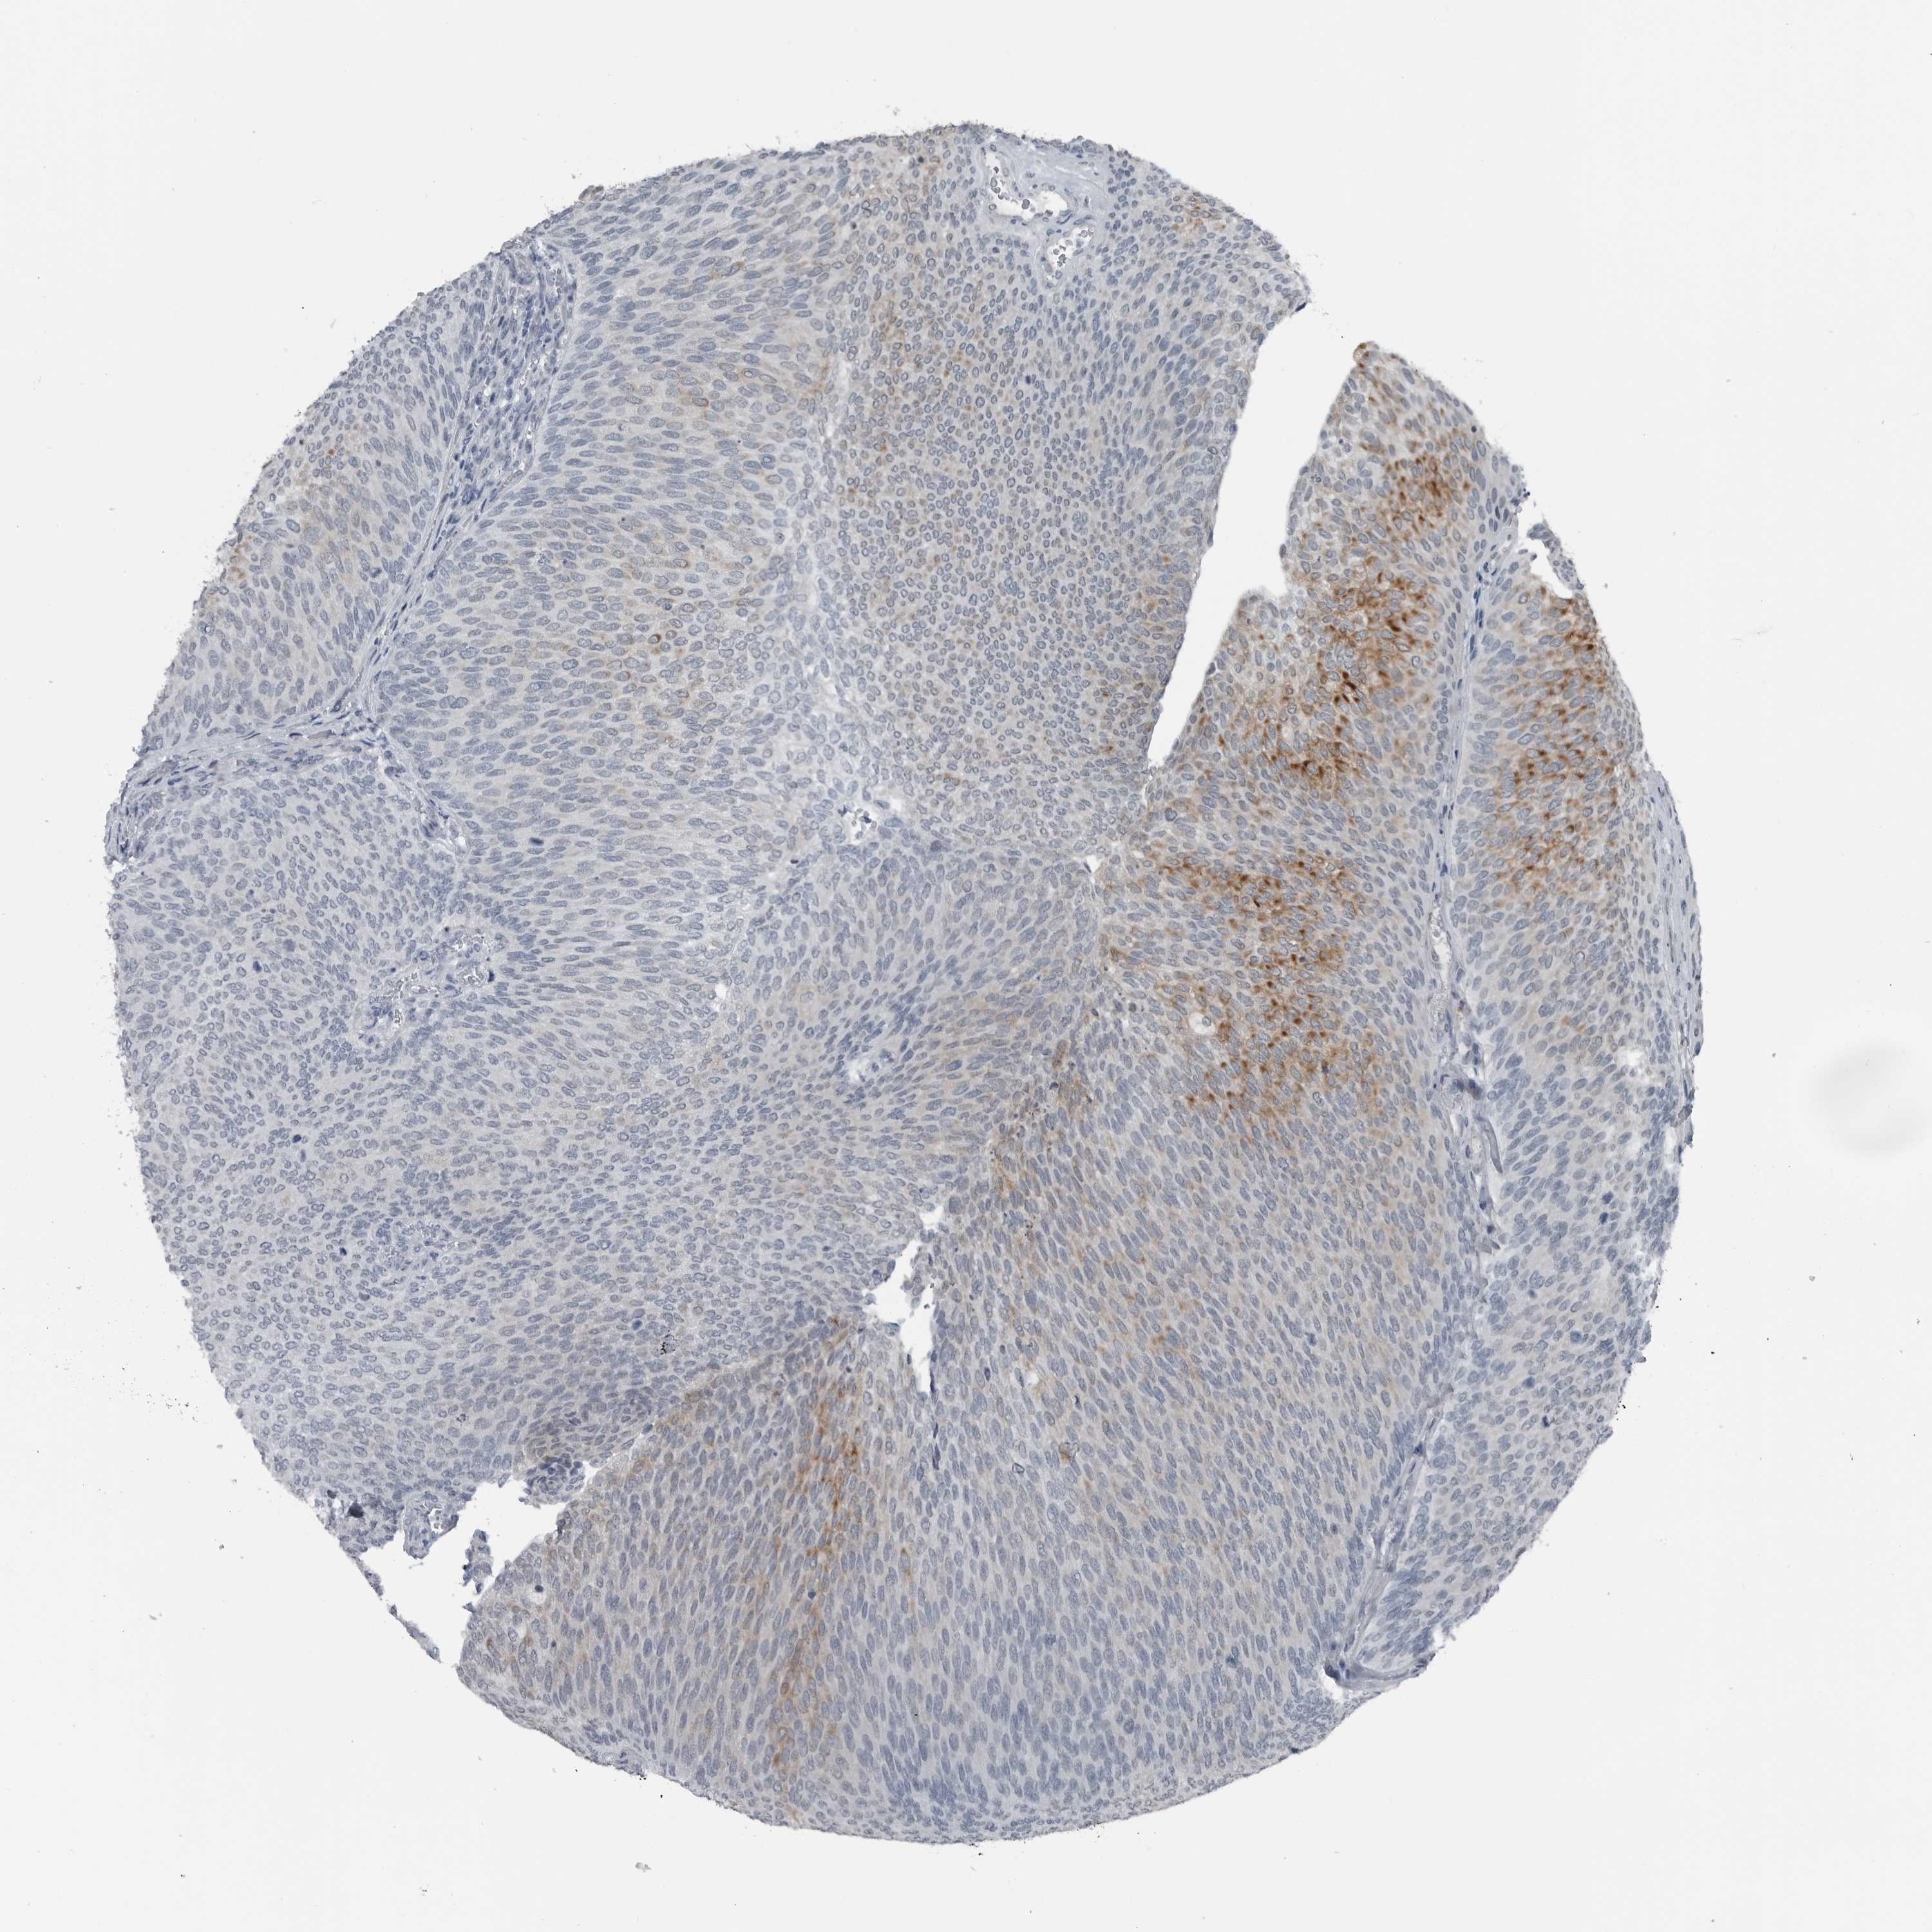

UROTHELIAL CANCER - Protein expressioni

A mouse-over function shows sample information and annotation data. Click on an image to view it in a full screen mode. Samples can be filtered based on level of antibody staining by selecting one or several of the following categories: high, medium, low and not detected. The assay and annotation is described here.

Note that samples used for immunohistochemistry by the Human Protein Atlas do not correspond to samples in the TCGA dataset.

Antibody stainingi

Antibody staining in the annotated cell types in the current human tissue is reported as not detected, low, medium, or high, based on conventional immunohistochemistry profiling in selected tissues. This score is based on the combination of the staining intensity and fraction of stained cells.

Each image is clickable and will lead to virtual microscopy that enables deeper exploration of all samples and also displays staining intensity scores, fraction scores and subcellular localization as well as patient and tissue information for each sample.

Antibody HPA027405

Antibody HPA027459

Antibody HPA027463

Staining

High

Medium

Low

Not detected

Intensity

Strong

Moderate

Weak

Negative

Quantity

>75%

75%-25%

<25%

None

Location

Nuclear

Cytoplasmic/membranous

Cytoplasmic/membranous,nuclear

Urothelial carcinoma, Low grade

Urothelial carcinoma, High grade